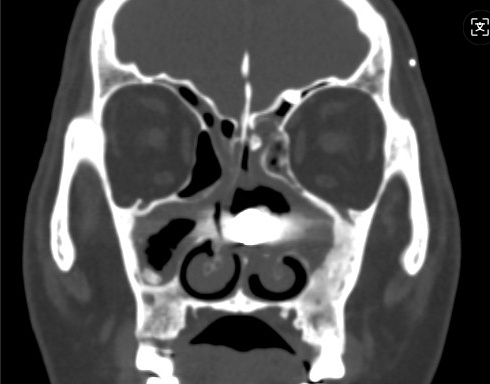

CT检查印证了推断:左侧鼻腔内果然有一高密度异物!

3月10日,邹帆专家团队在全麻下为其实施手术。由于异物留存太久,已被肉芽组织紧紧包裹,手术难度陡增。但凭借精准操作,团队仅用35分钟,就将一枚长约3厘米的螺丝钉完整取出。